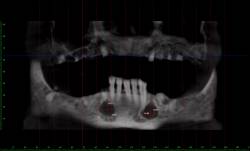

3D Образна диагностика

-мандибула

Planmeca PROMAX 3D е подходящ за множество диагностични изисквания: тези на ендодонтията, пародонта,

ортодонтия, имплантология, лицево-челюстната хирургия и анализ на Темперомандибуларна става. Системата

има софтуер и технология за изследване на синуси, средно ухо, череп, челюсти.

Предимството на този метод е, че при изследването на синуси и челюсти, наличните метални

коронки,

мостове и импланти не влошават качеството на получените изображения.